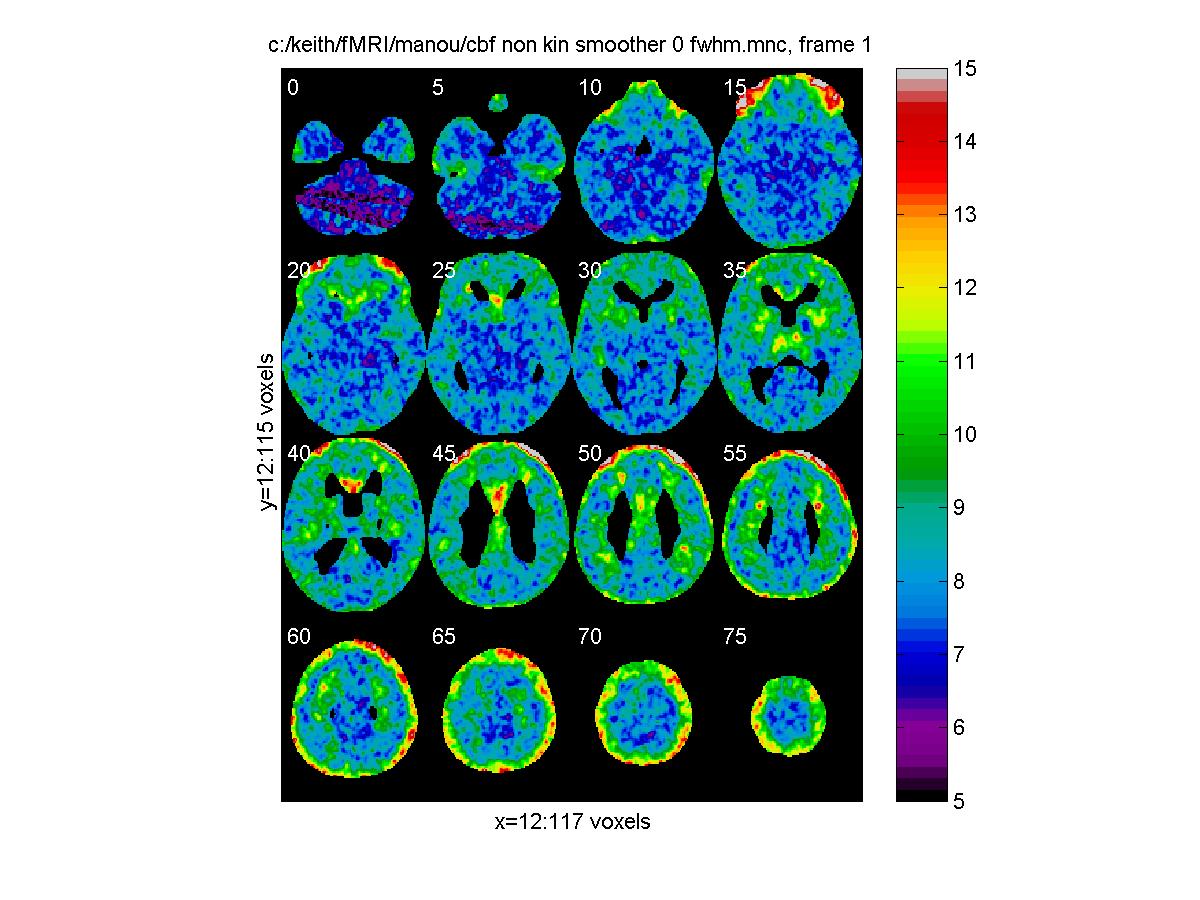

To look at the results, we can choose the overall average effect as a mask, which we can threshold at say 0.65 (half its maximum). Then we can again use view_slices to take a look at every 5th slice through the volume of say task 3. For the effect of task 3 - baseline (in units of normalized cbf):

mask='c:/keith/fMRI/manou/cbf_non_kin_smoother_0_ef.mnc'

clf;

view_slices('c:/keith/fMRI/manou/cbf_non_kin_smoother_3_ef.mnc',mask,0.65,[0:5:79])

![[Click to enlarge image]](figs_pet_tn/fignormef.jpg)

Standard error, in units of normalized cbf:

view_slices('c:/keith/fMRI/manou/cbf_non_kin_smoother_3_sd.mnc',mask,0.65,[0:5:79])

![[Click to enlarge image]](figs_pet_tn/fignormsd.jpg)